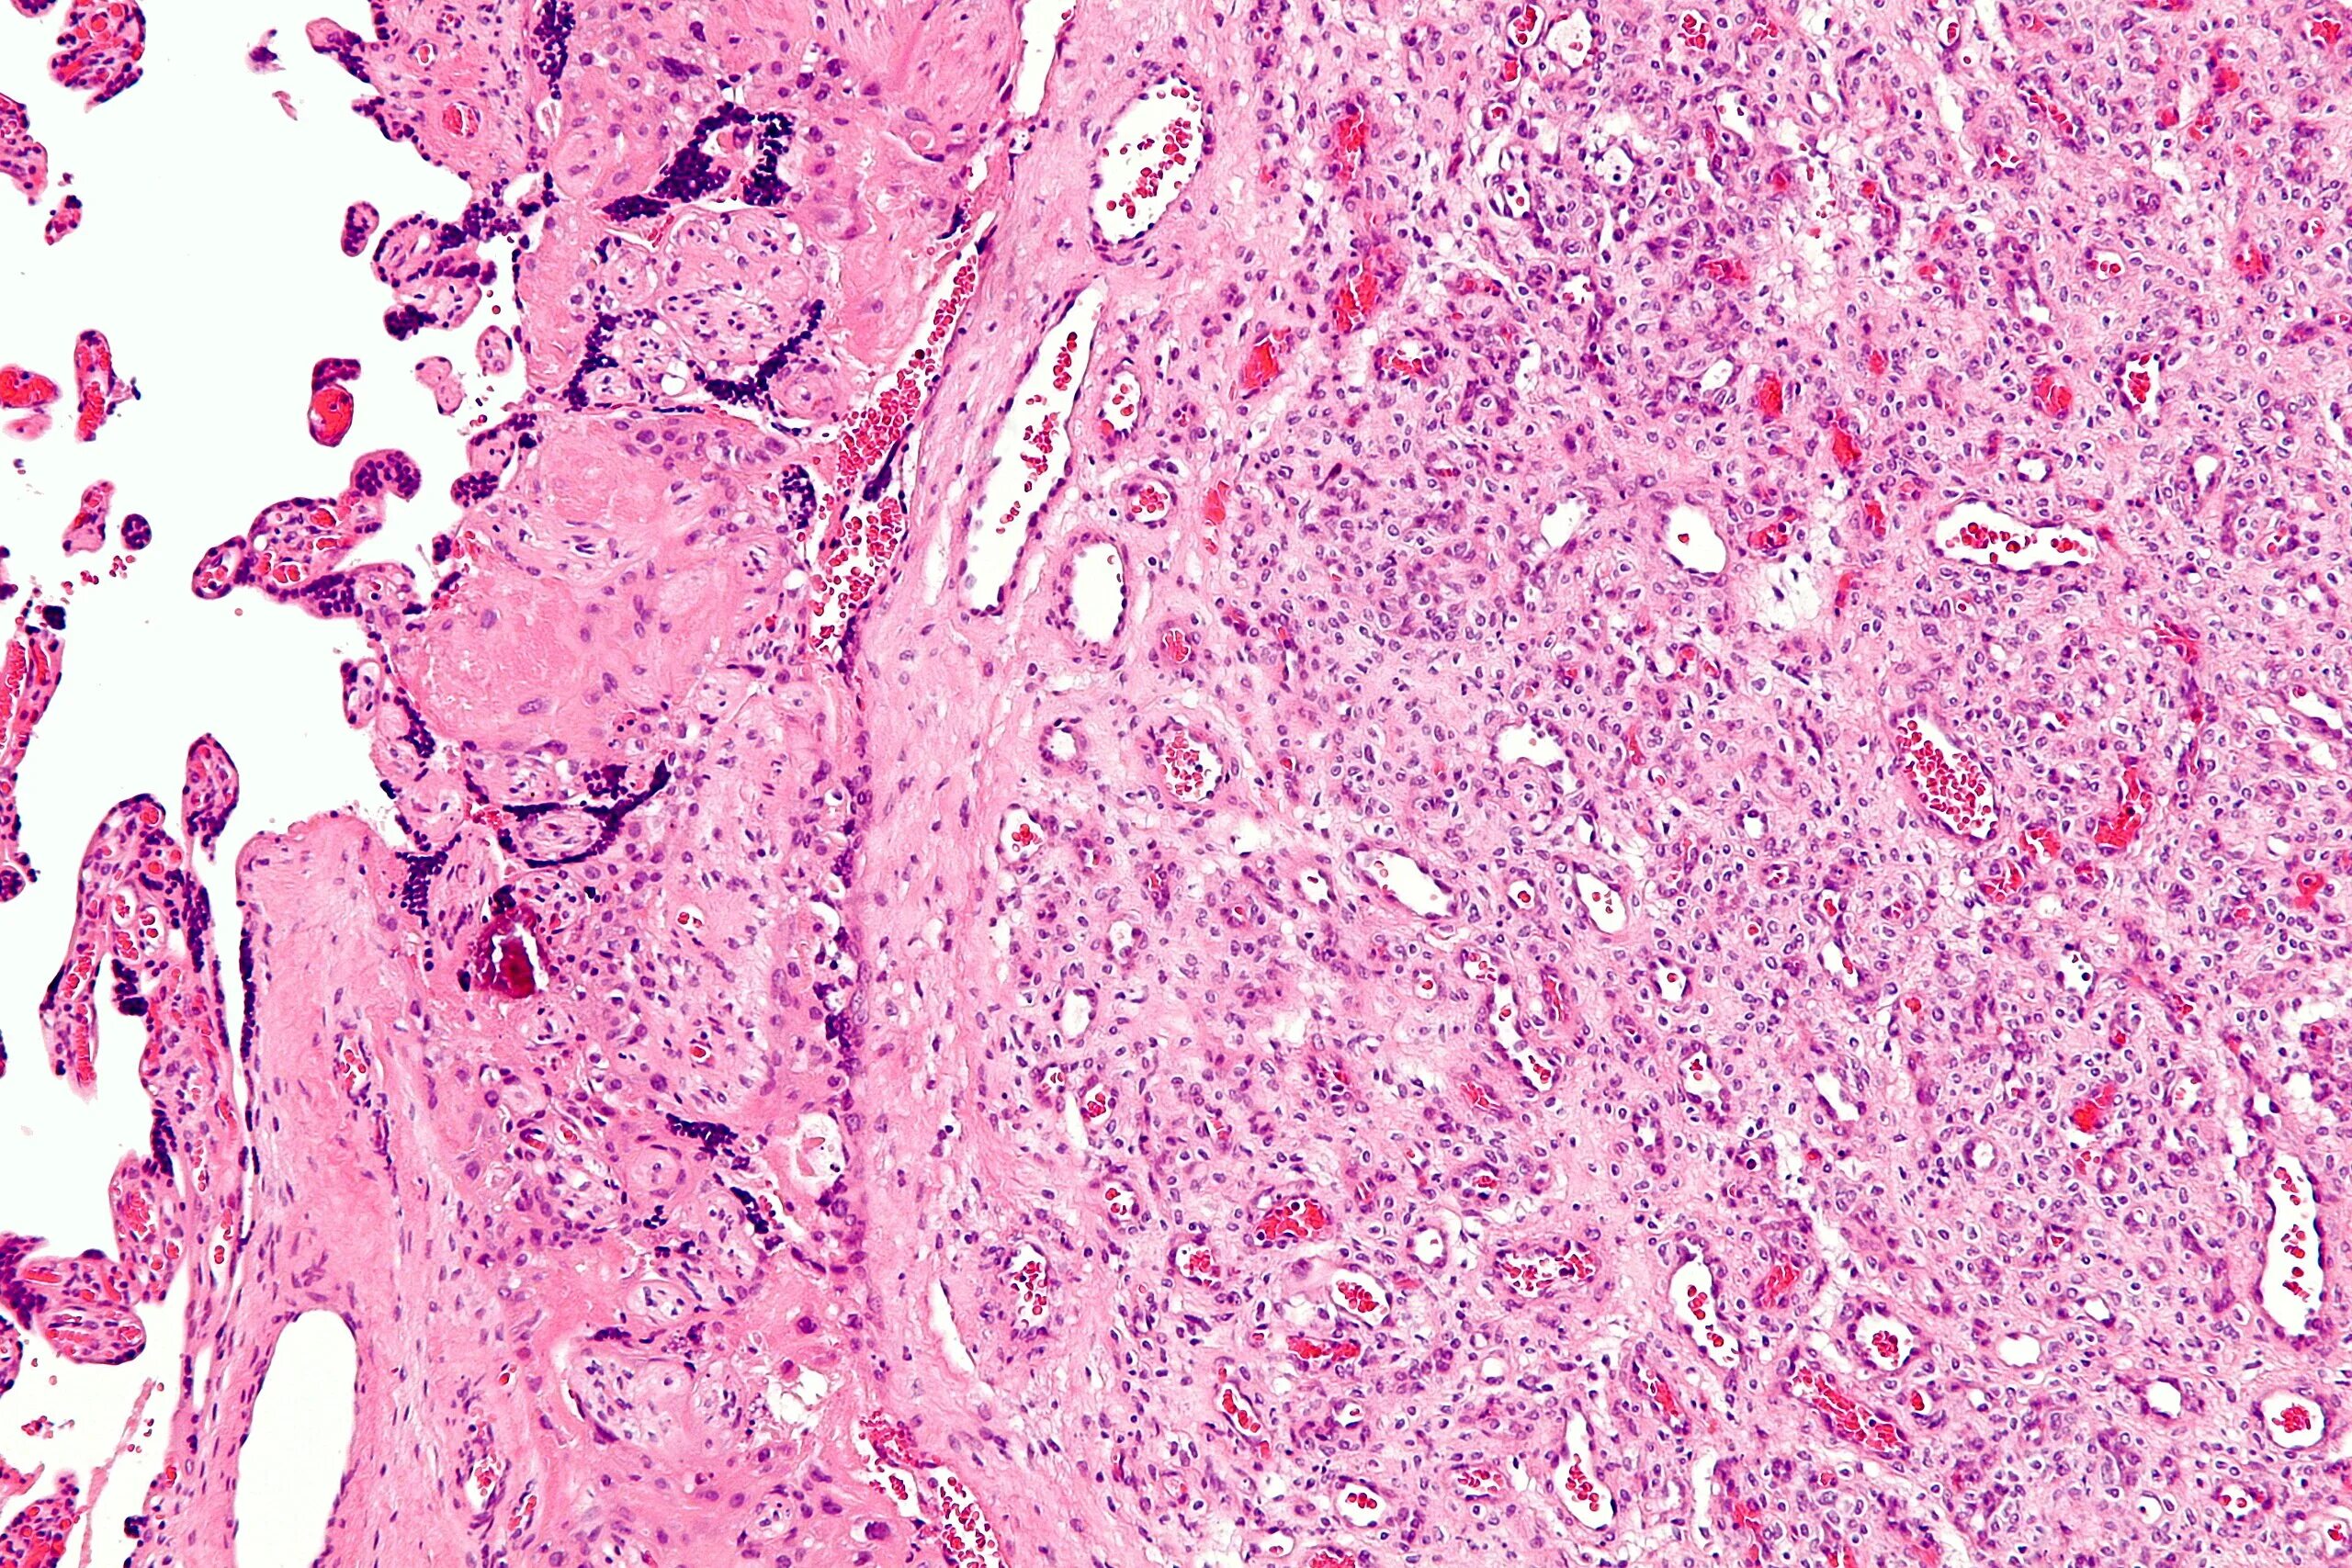

Гистология э